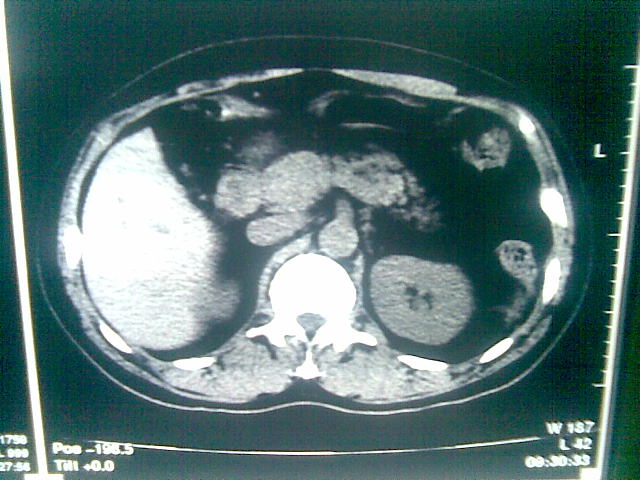

标题: CT23981:男,38岁阑尾炎术后透视胸腔积夜!做CT如下!积液包 [打印本页]

标题: CT23981:男,38岁阑尾炎术后透视胸腔积夜!做CT如下!积液包

可能与阑尾术后关系不太大,1.胸膜增厚粘连见少量气体。包裹脓气胸?左侧网膜囊脓肿?

少量积液部分粘连

左侧胸膜增厚、粘连+包裹液气胸。